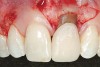

A 54-year-old non-smoking woman presented for correction of deep-wide gingival recession in the maxillary anterior (Figure 1 through Figure 3). The patient’s desires were to correct the gingival recession, balance the heights of contour of the tissues, and possibly undergo esthetic enhancement of the maxillary anterior with veneer restorations.

Figure 1  Case One Pretreatment clinical view, Case 1, maxillary right.

Figure 1

Figure 2  Case One Pretreatment clinical view, Case 1, maxillary anterior.

Figure 2